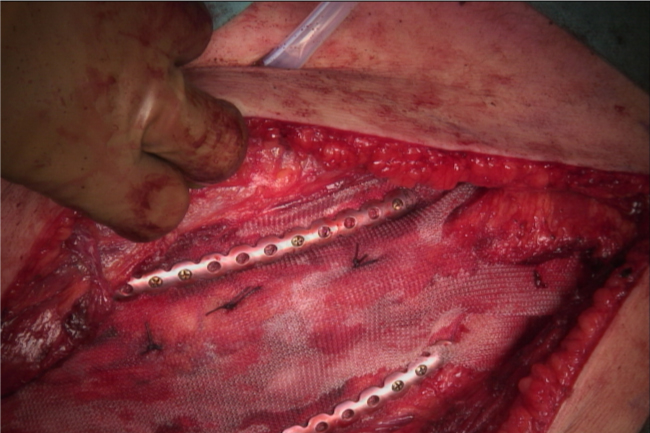

A 63 year old male with a history of smoking, COPD (GOLD I) and a diagnostic laparotomy for suspected small bowel pathology followed by multiple abdominal hernia repair operations of the lower abdomen, presented at the GP with chest pain during coughing spells. The coughing spells started several weeks ago. Though anamnesis revealed no prior trauma, a chest x-ray showed rib fractures of the 7th, 8th and 9th ribs on the right side, accompanied by herniation of lung tissue between ribs 7 and 8 (Figure 1a). A CT-scan of the chest confirmed the diagnosis of a lung herniation (Figure 1b). Vital signs were normal, however breathing was laboured with an increased respiratory rate. The patient was admitted to the Intensive Care Unit (ICU) for observation and pain management. He developed mild to moderate dyspnoea due to inadequate respiration, caused by pain for which an epidural catheter was placed. Because of further clinical decline the patient was planned for surgery. During the procedure a significant hernia sac covert by parietal pleura was found (Figure 1c). The rib cage was reconstructed using plates and vicryl sutures. Next, a polypropylene mesh was placed between the ribs for reinforcement (Figure 1d). There were no postoperative complications and in the next few days a full recovery followed. One year after surgery the patient was in good health and reported to have no discomfort during respiration or other physical discomfort.

Figure 1d: Intraoperative photograph showing reconstruction of the chest wall using the MatrixRIB™ fixation system in combination with a Marlex polypropylene mesh. View Figure 1d